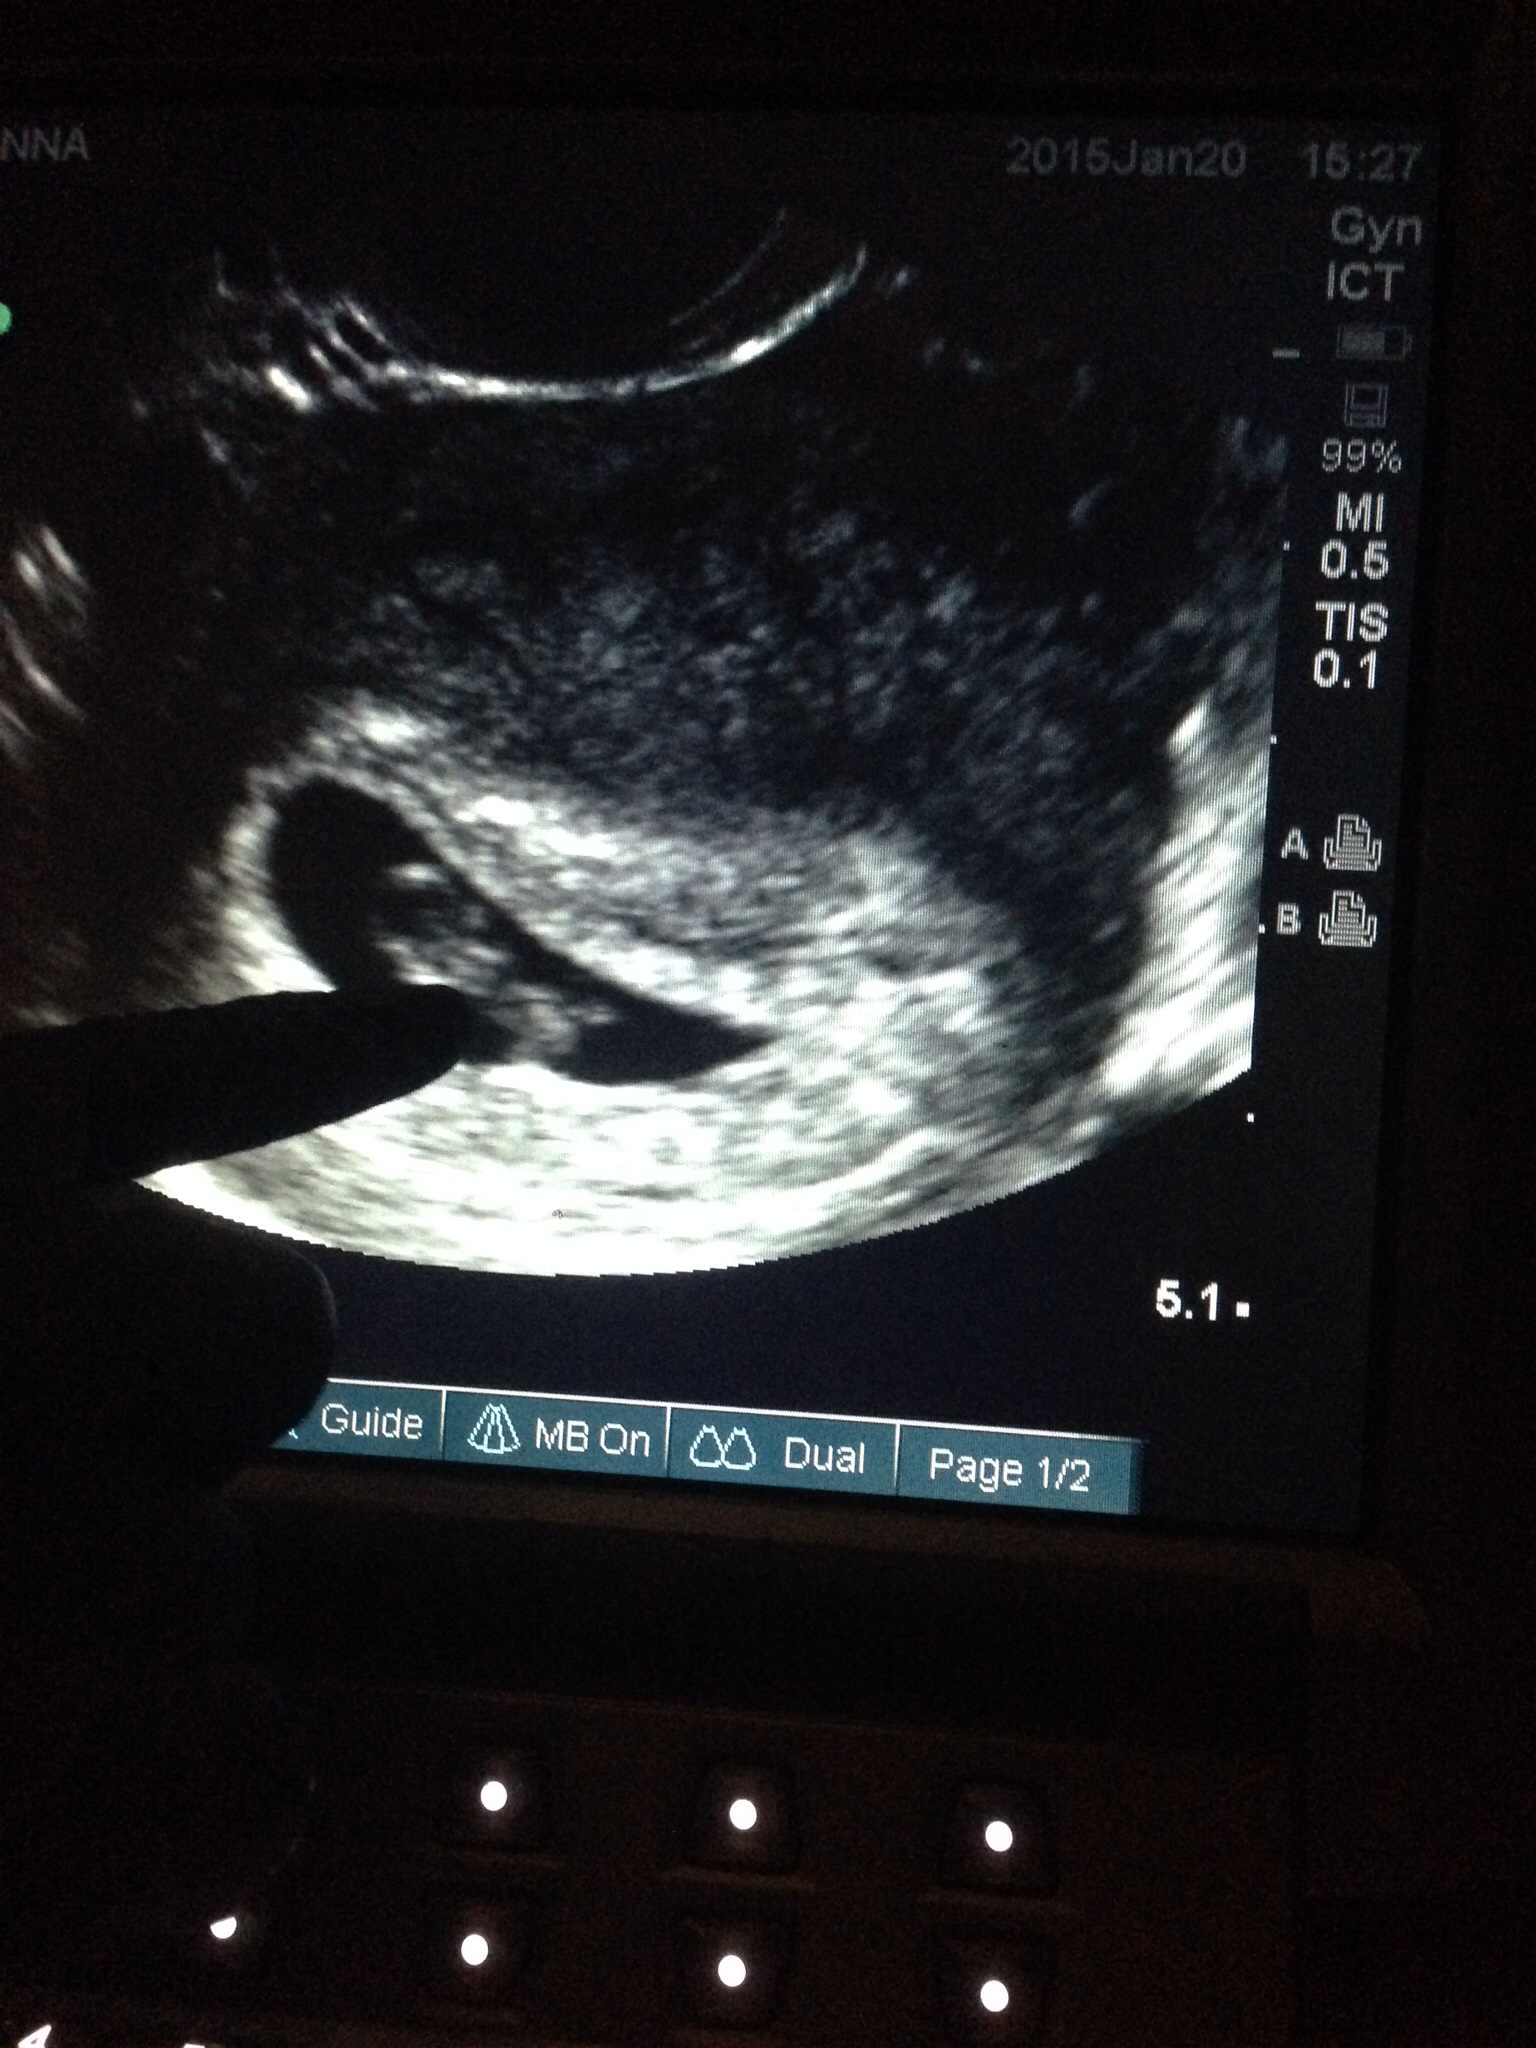

I just had my first appt and u/s today!! I am 6w5d. I thought I was 7w4d but my OB told me 6 weeks. So happy! Got to see our little bundle of joy and hear the heartbeat!

First US today. Thought I was 7wks 3days turns out measuring 6wks 1day heart beat 122bpm. Not sure how I feel about the new time frame cause now I have to keep it under wraps longer.

I had my first ultrasound this morning. Based on LMP I should have been 8 weeks today. I know I ovulated really late. Only measured at 6 weeks 6 days with a heart rate of 146 bpm. So very happy to see that tiny flutter!!!